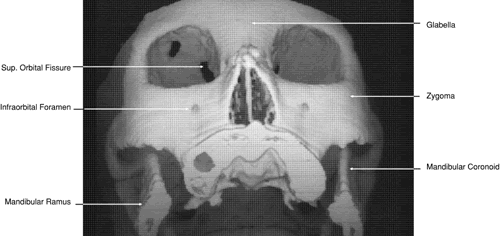

The globe is shown in Figure 12. The orbit and periorbital structures are shown in Figures 13 through 16, and the optic canal is shown in Figures 17 through 26. The cavernous sinus and optic chiasm are shown in Figures 27 and 28, and the posterior visual pathway and cranial nerves are shown in Figures 29 through 33.

Fig. 29. A. Axial computed tomography soft tissue image at the level of the base of skull. B. Axial computed tomography bone window image at the level of the base of skull.